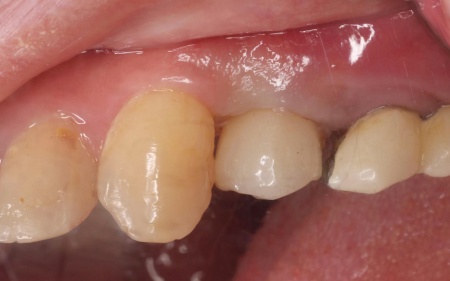

拝見したところ、左上奥歯(第1小臼歯)は歯の上の部分である歯冠が折れ、歯根のみ残っている状態でした。

また、左下奥歯(第2小臼歯)には被せ物が装着されています。

診断結果をお伝えし、患者様の了承を得たうえで左下奥歯の被せ物を外したところ、レントゲン検査での診断どおり、歯根が割れていることが確認できました。

後日、完成した人工歯をインプラントに装着し、使用感や見た目に問題がないことを確認して、治療を終了しました。